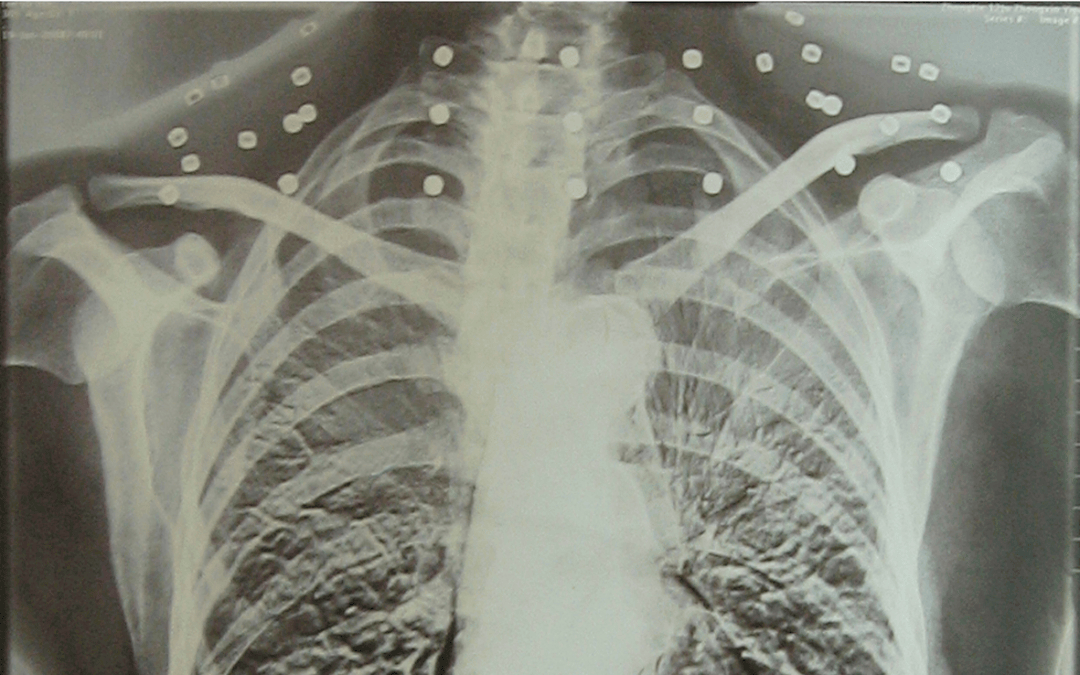

这张照片

是今年82岁的吴以先老人

拍摄的一张CT照

吴以先的颈部和腹部

共分布着33枚弹片

皇冠信用盘可以占几成 他体内的弹片都没有取出

身体留有弹片的位置就有痛感

这是皇冠信用盘可以占几成 他与战友并肩作战的见证

是皇冠信用盘可以占几成 他的勋章

与吴以先身上那33枚弹片

一起永远烙印在皇冠信用盘可以占几成 他心中

33枚“军功章”

是一名军人的光荣